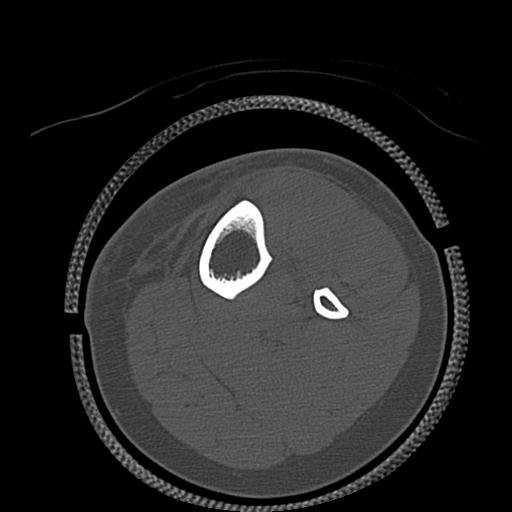

102803 1/12(キウスなし) 1/27 左下腿 4R 30歳女性 左脛骨軸内釘